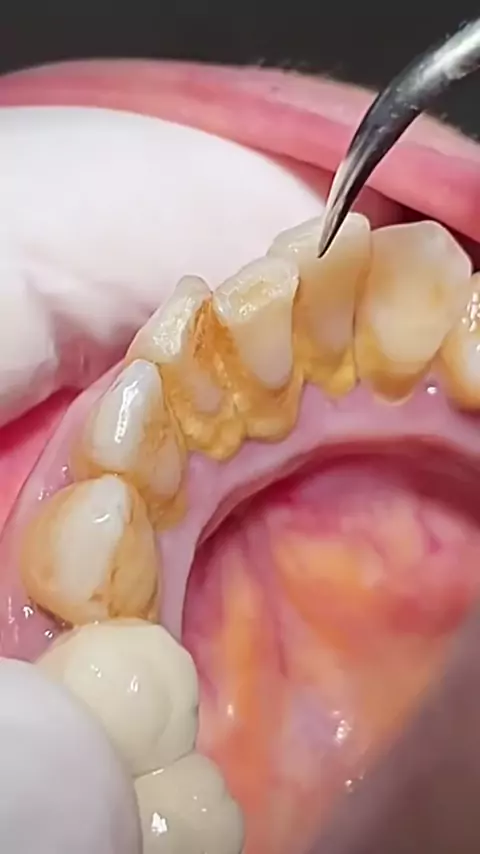

Sua limpeza dental está em dia? Placa e tártaro causam gengivite, mau hálito e até perda dentária. A limpeza previne esses problemas e permite detectar alterações antes que virem dor de cabeça. Se você não lembra da última vez que fez, já passou da hora. Agende sua avaliação! #clidonto #limpezadental #saudebucal #dentistaemsantoantoniodejesus #sorrisosaudavel